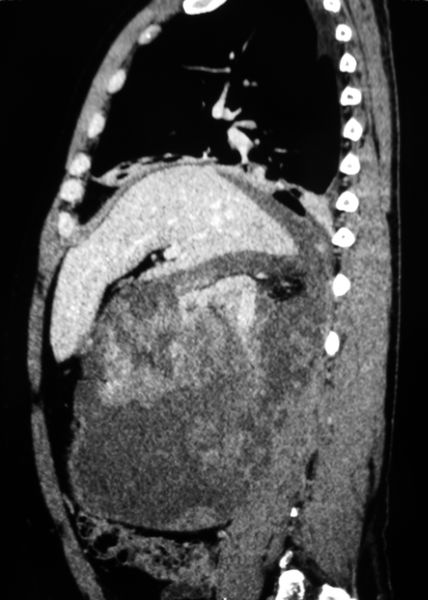

Огромная опухоль правой почки

Гигантская опухоль правой почки. Экстримальная нефрэктомия.